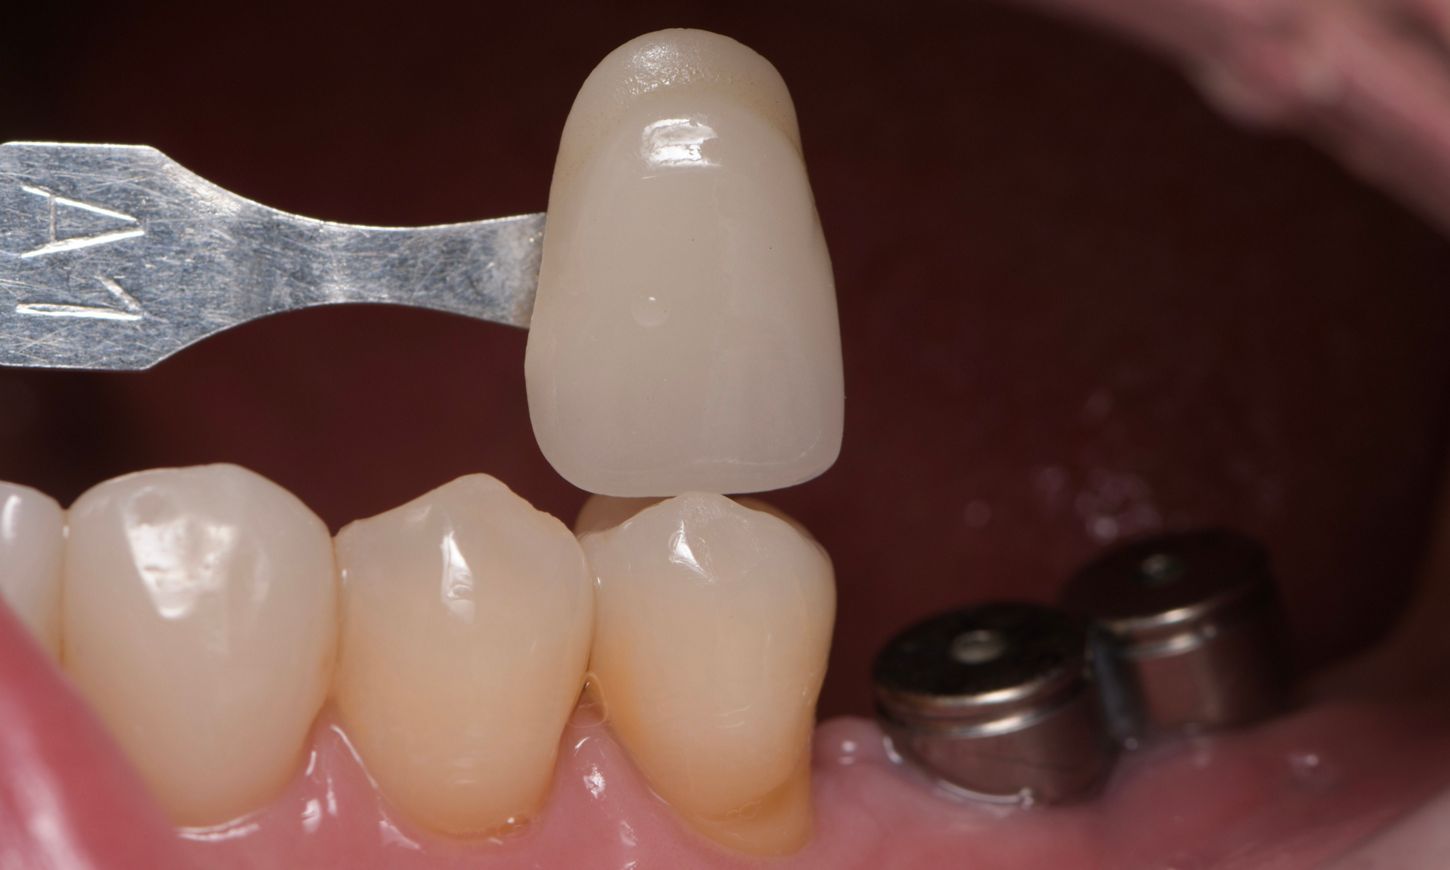

Prosthetic procedure

After the healing period, the next step involved selection of the appropriate shade for the fully polished zirconia prosthetic to ensure esthetic integration with the surrounding natural dentition. To achieve a precise match and optimal visual outcome, a shade guide was used, and the selected shade was confirmed with the patient (Fig. 17). An impression was taken with the open-tray technique, using addition silicone material for its high dimensional stability and accuracy (Fig. 18). Then it was sent to the dental laboratory for the fabrication of the final prosthesis.

Fig. 17

Fig. 18

The gingiva was evaluated before the placement of the final prosthetics (Fig. 19). A fully polished zirconia prosthetic was then carefully fabricated and inserted, and torqued to 35 Ncm (Figs. 20,21) and the subsequent x-ray revealed satisfactory results (Fig. 22).